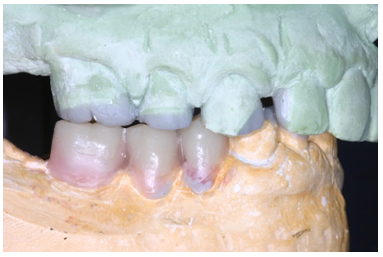

The final preparations were observed in two study casts to improve the parallelism and ensure accurate path of the insertion for the final prostheses. Final preparations and relining of the provisional restorations followed. Final impressions were performed using polyvinyl-siloxane (Aquasil, Dentsply, Germany) with the two-step double mixing technique (stock tray, double cord technique) in the maxilla. Mandibular impression was performed with an open tray technique combining implant and teeth abutments with polyether material (Impregum, 3M, USA). In next appointment the accuracy of final casts was examined and jaw relation recordings were performed. The position of maxillary cast was transferred with a Whip-Mix face bow and centric relation (CR) was registered with a custom made acrylic Lucia jig (anterior deprogrammer) and an implant retained base plate in the mandible to ensure accurate registration. Dental and implant abutments metal try-in were completed in two steps (Figure 16). After thorough verification of accuracy of fit and jaw registrations, ceramic veneering was checked for proper occlusion (Figure 17,18). Finally all restorations were cemented with adhesive resin cement (Panavia F2.0, Kuraray, Japan), except for the implant restorations which were cemented with a provisional cement (Temp-bond, Kerr, Germany).

Figure 16: Dental abutments metal try in the maxilla.

Figure 17: Final restorations occlusal view of the maxilla.

Figure 18: Final restorations occlusal view of the mandible.